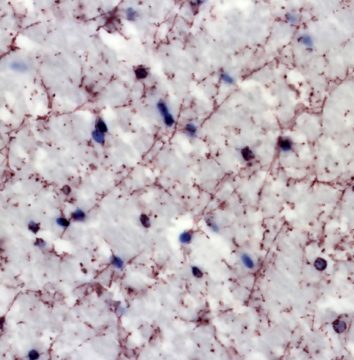

© Andry Andrianarivelo and Peter Vanhoutte—Neuroscience Paris Seine laboratory (CNRS / Sorbonne University / INSERM)

Drug addiction is a psychiatric disorder for which no pharmacological treatment with long-term efficacy currently exists. All addictive substances share the property of raising concentrations of the neurotransmitter dopamine within brain regions forming the neural reward circuit. This increase in dopamine levels results in long-lasting alteration of signal transmission that is dependent on another neurotransmitter, glutamate, which causes addictive behaviours.

Through a new study, an international team including scientists from the CNRS, INRAE, the CEA, Sorbonne University, Paris-Saclay University, the University of Bordeaux, and Université Côte d’Azur* has uncovered, in mice and humans, the molecular bases of this deleterious interplay between dopamine and glutamate. The researchers’ work shows that the inhibition of interactions between dopamine and glutamate receptors prevents pathological behaviours provoked by cocaine in mice, without altering natural reward processing. Their findings, published in Science Advances (20 October 2021), pave the way for the development of new therapeutic strategies to treat addiction, and a wider spectrum of psychiatric disorders.

Disrupting D1-NMDA or D2-NMDA receptor heteromerization prevents cocaine’s rewarding effects but preserves natural reward processing.